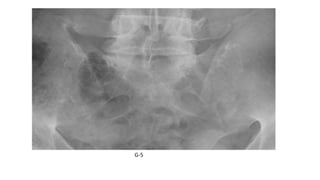

Grading of Sacroiliitis: New York Criteria

• Grade 0: normal

• Grade 1: suspicious -some blurring of the joint margins

• Grade 2: Minimal abnormality with small areas of erosions or

sclerosis without alteration in the joint width

• Grade 3: Unequivocal abnormality - moderate or advanced sacroiliitis

consisting of erosion, sclerosis, widening, narrowing, and/or partial

joint fusion (ankylosis)

• Grade 4: Complete ankylosis

G-5